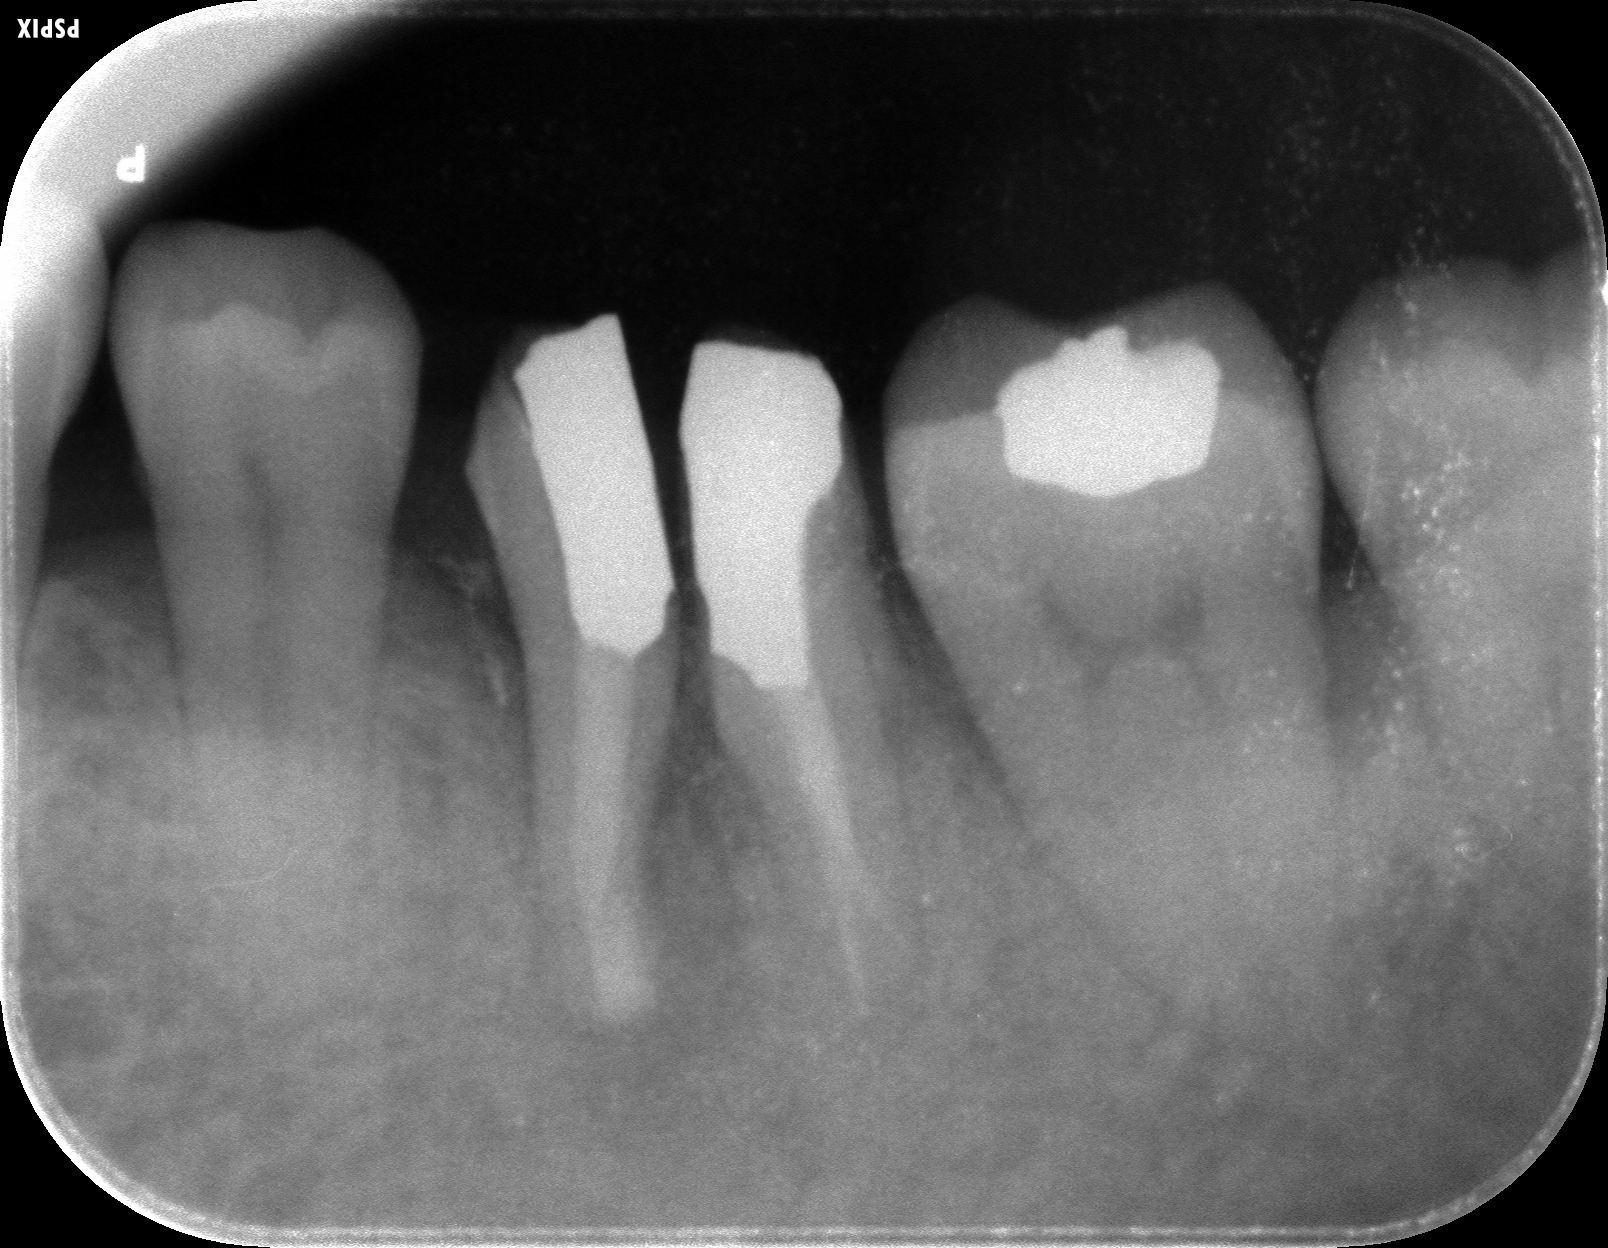

術前のレントゲン写真です。

根の先に膿の袋があります。(レントゲン透過像)

術直後です。

悪い組織を掻き出したばかりのため根の周りはまだ黒くなっています。

術後3ヶ月でのレントゲン写真です。

術後の経過は良好で、根尖部の透過像(膿の袋)は無くなりました。